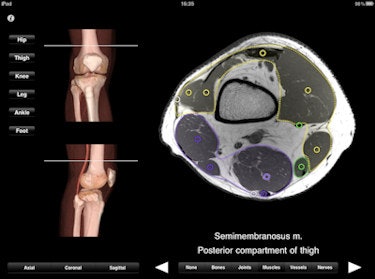

Monster Anatomy Lower Limb offers 384 MRI slices that can be viewed in the sagittal, coronal, and axial planes and includes a 3D display of the region of interest with a line indicating the level of the MRI slice being viewed.

The upper limb app allows users to scroll through 500 MRI slices at intervals of 2-4 mm.

The lower limb app offers 384 MRI slices that can be viewed in sagittal, coronal, and axial planes.While the app is not yet Gray's Anatomy, the group clearly plans to build on its first-to-Internet lead as the online anatomical reference source. In partnership with the university and the university hospital (CHU-Nancy), Monster Minds Media was formed in November 2010 to continue development of modules covering other regions of the human body under the direction of Louis, now a radiologist practicing with Guilloz Imaging Services.